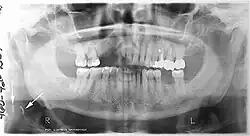

Panoramic radiograph

A dental panoramic radiograph, showing the maxilla and mandible, all the teeth including the "wisdom teeth," the frontal and maxillary sinuses, the nasal cavity and the temporomandibular joint and other near by head and neck anatomy. | |

A panoramic radiograph is a panoramic scanning dental X-ray of the upper and lower jaw. It shows a two-dimensional view of a half-circle from ear to ear. Panoramic radiography is a form of focal plane tomography; thus, images of multiple planes are taken to make up the composite panoramic image, where the maxilla and mandible are in the focal trough and the structures that are superficial and deep to the trough are blurred.

Panoramic radiographs have the capability to demonstrate a portion of the neck and display atheromas (calcifications in the carotid artery) which are an indication of both local and generalized (systemic) atherosclerosis. Atherosclerosis of the coronary arteries leading to myocardial infarction (heart attack), and atherosclerosis of the carotid artery leading to stroke are the number one and number three most common causes of death in the United States.[6]